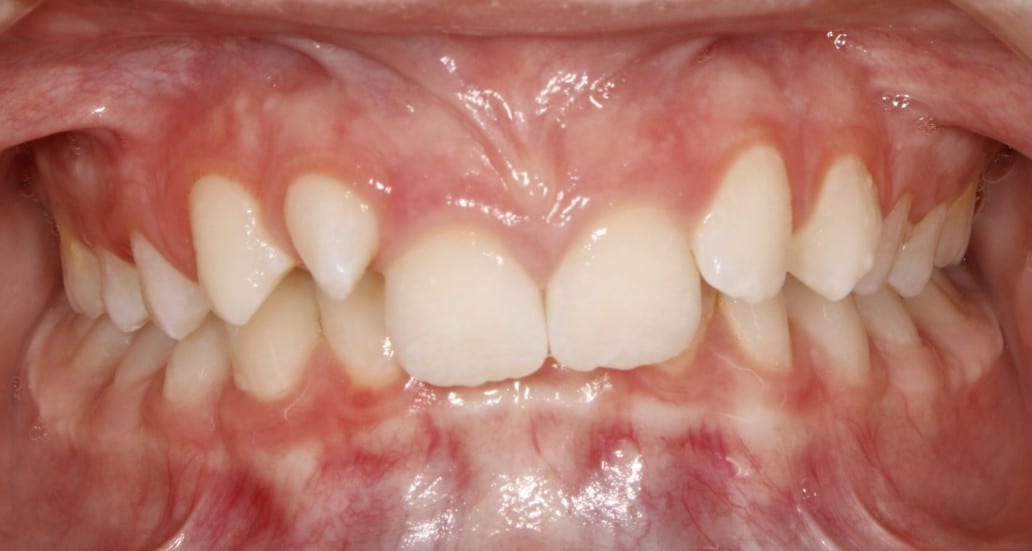

Teenage patient treated with fixed braces and orthognathic surgery